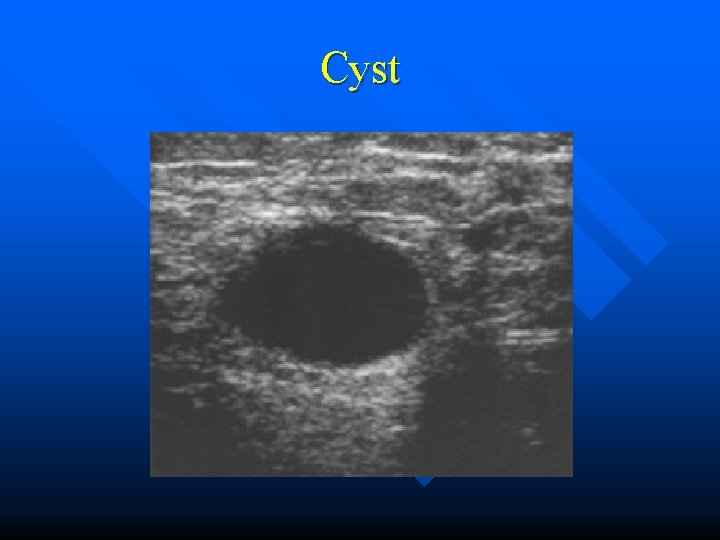

SONOGRAPHY n • • • Indications: Exclusion of a simple cysts Detection of malignancy in the presence of uncharacteristic and questionable palpatory findings in mamographycally dense tissue. Sonographically guided puncture)

Image presentation of the breast Ca • • Hypoechoic, often with varying echogenicity throughout the mass. Poorly to moderately compressible or moveable Irregularly out; ined with or without hyperechoic rim. With or without acoustic shadow.

Cyst